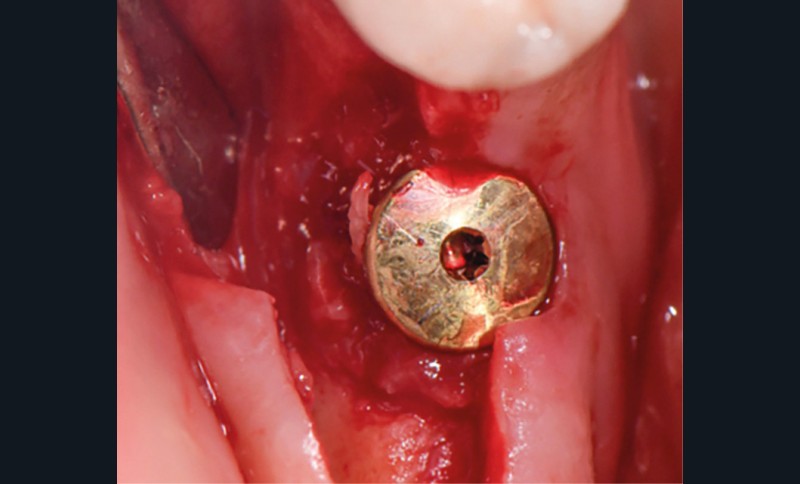

Actes préopératoires

La couronne a été déposée et une vis de couverture mise en place. La patiente a reçu un nettoyage supra-gingival général avec une attention particulière pour l’implant 47, et une irrigation locale avec du gel de chlorhexidine et du peroxyde d’hydrogène pour réduire l’inflammation des tissus. De l’amoxicilline (3 x 500 mg) a été prescrite, à commencer la veille de l’intervention chirurgicale.